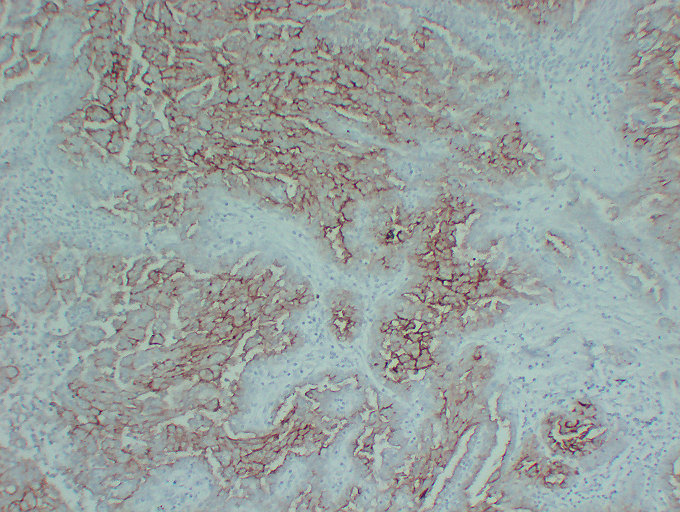

Immunohistochemistry analysis of paraffin-embedded Human Mesothelioma using Mucin 16 antibody.High-pressure and temperature Sodium Citrate pH 6.0 was used for antigen retrieval.

Immunohistochemistry analysis of paraffin-embedded Human Ovarian serous cystadenoma using Mucin 16 antibody.High-pressure and temperature Sodium Citrate pH 6.0 was used for antigen retrieval.